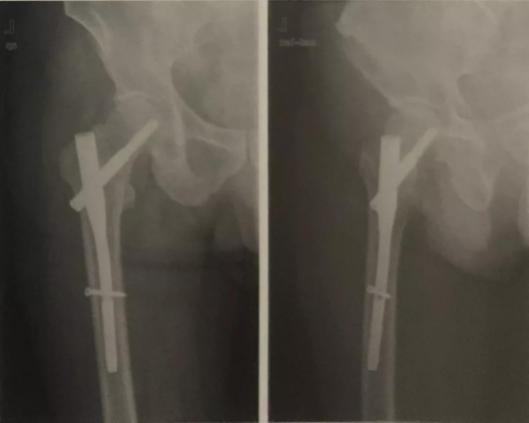

再次,您的手术需要固定吗?骨折一般需要使用内、外固定器械对骨折端进行固定,骨科常用的固定器材有钢板、螺钉、髓内钉、外固定架等种类繁多,而不同部位的骨折,不一样的骨折形态所需的固定器械又不尽相同,这就需要医生们制定详细的手术方案,充分考虑术前、术中、术后可能发生的各种突发情况,挑选出最适合病人的固定器械,这也是原因之一。

那么何时手术?晚几天手术会影响预后吗? 对于闭合性骨折,到达医院时已经出现了肿胀,最好是等消肿后再手术治疗。如果没有起水泡,待局部皮肤出现皱褶即可安排手术;如果出现水泡,应待水泡消退后再手术。临床结果显示:伤后两周内手术对骨折愈合及术后康复没有影响。当然随着时间推移,术中复位难度会增加。权衡利弊,保护软组织比难复位更重要,“皮之不存,毛将焉附?”同理,软组织修复不好,骨头咋能长好?